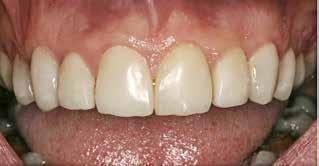

Fig. 1. 40-årig sund og rask mand møder bekymret for sine slidte tænder. Klinisk ses frakturer og substanstab langs incisalkanterne på overkæbetænderne.

Fig. 1. A 40-year-old healthy man is concerned for his worn teeth. Clinically, fractures and loss of tooth substance are observed at the incisal edge of the upper front teeth.